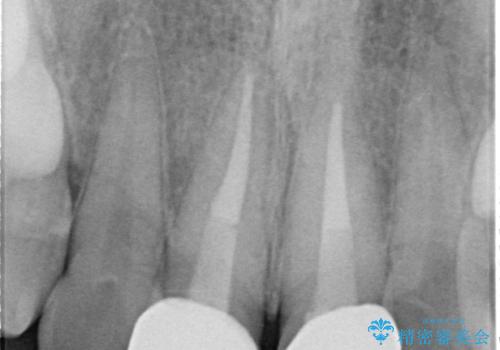

- 以前、保険診療で治療を受けた前歯の見た目が気になるとのことで来院された患者様です。

転倒時に前歯2本が折れてしまい、すでに根管治療(神経の治療)が行われている状態でした。

診査の結果、噛み合わせが深い「ディープバイト」の状態であり、下の前歯には叢生(歯並びのデコボコ)も認められました。

噛み合わせを改善するための矯正治療をご提案しましたが、患者様のご希望により矯正治療と根管治療の再治療は行わず、ファイバーコア(土台)+オールセラミッククラウンによる補綴治療を選択しました。

審美性と強度を両立させるため、透明感のあるオールセラミッククラウンを採用し、周囲の天然歯に自然に調和するよう色調・形態を調整しました。